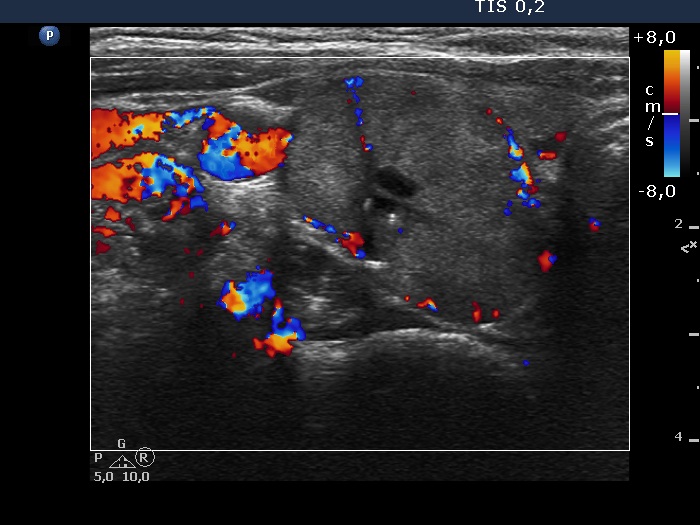

Right lobe, longitudinal scan

Right lobe, transverse scan, color Doppler mode. The lesion has perinodular blood flow.